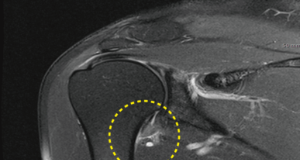

2) 동결견 초기에는 회전근 개 질환과 구별이 어려울 수 있지만, 시간이 지날수록 뚜렷한 차이가 나타납니다. 또한, 견갑 흉곽 운동이 주로 나타나면서 움직임에 "덜컹" 거리는 느낌이 생길 수 있습니다.

물리 치료에도 불구하고 증상이 심한 경우 수술적 치료가 고려될 수 있습니다. 관절경술은 관절내 생리 식염수 주입, 이상 병변 제거술, 세척술 등을 통해 관절낭을 팽창시키고 동반된 병변을 조사하여 적절한 치료를 시행할 수 있습니다. 이는 임상에서 확인되지 못한 병변을 발견하는 잇점이 있습니다.